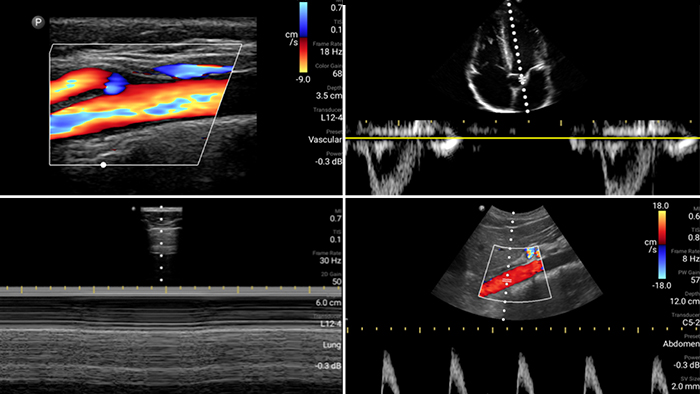

Evaluate, diagnose and treat your patients in minutes with a multi-point POCUS exam.

Lumify can help assess patients faster and improve accuracy when diagnosing common causes of dyspnea and other lung conditions.

Get the full picture with clear whole-body imagery for a fast, accurate response during an emergency.

• 4 to 1 MHz extended operating frequency range • 2D, color Doppler, M-mode, advanced XRES and multivariate harmonic imaging • High-resolution imaging for abdominal and cardiac applications: Cardiac, OB/GYN, Lung, Abdomen and FAST imaging preset optimizations Lumify aids life-saving technology in prehospital setting